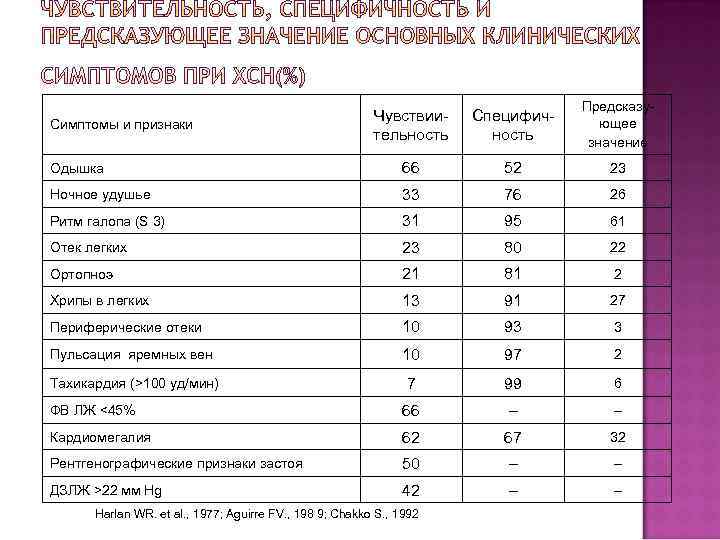

Чувствиительность Специфичность Предсказующее значение Одышка 66 52 23 Ночное удушье 33 76 26 Ритм галопа (S 3) 31 95 61 Отек легких 23 80 22 Ортопноэ 21 81 2 Хрипы в легких 13 91 27 Периферические отеки 10 93 3 Пульсация яремных вен 10 97 2 Тахикардия (>100 уд/мин) 7 99 6 ФВ ЛЖ <45% 66 – – Кардиомегалия 62 67 32 Рентгенографические признаки застоя 50 – – ДЗЛЖ >22 мм Hg 42 – – Симптомы и признаки Harlan WR. et al. , 1977; Aguirre FV. , 198 9; Chakko S. , 1992

Чувствиительность Специфичность Предсказующее значение Одышка 66 52 23 Ночное удушье 33 76 26 Ритм галопа (S 3) 31 95 61 Отек легких 23 80 22 Ортопноэ 21 81 2 Хрипы в легких 13 91 27 Периферические отеки 10 93 3 Пульсация яремных вен 10 97 2 Тахикардия (>100 уд/мин) 7 99 6 ФВ ЛЖ <45% 66 – – Кардиомегалия 62 67 32 Рентгенографические признаки застоя 50 – – ДЗЛЖ >22 мм Hg 42 – – Симптомы и признаки Harlan WR. et al. , 1977; Aguirre FV. , 198 9; Chakko S. , 1992